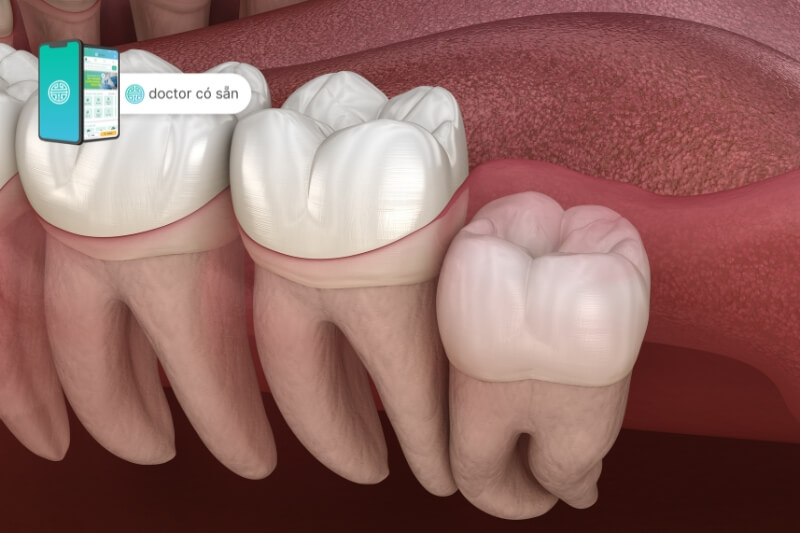

Ở những người có sự phát triển của răng khôn, việc nhổ răng khôn bị viêm nướu là tình trạng thường xuyên gặp. Bệnh viêm nướu răng khôn khi một phần của lợi ở hàm che phủ lên bề mặt của răng này, tạo ra môi trường không thuận lợi cho sự phát triển của nó. Khi răng khôn tiếp tục nảy mọc, nó sẽ chạm vào mô nướu, dẫn đến cảm giác đau và không thoải mái.

- Vị trí và cách răng khôn mọc: Nếu răng khôn mọc không đúng vị trí hoặc có góc mọc bất thường, nó có thể tạo ra sự cản trở với nướu xung quanh, gây viêm và sưng.

Trường hợp 1: Răng khôn mọc bình thường, không gây áp lực lên răng bên cạnh

Trường hợp 2: Răng khôn đang hoặc có thể ảnh hưởng đến răng bên cạnh